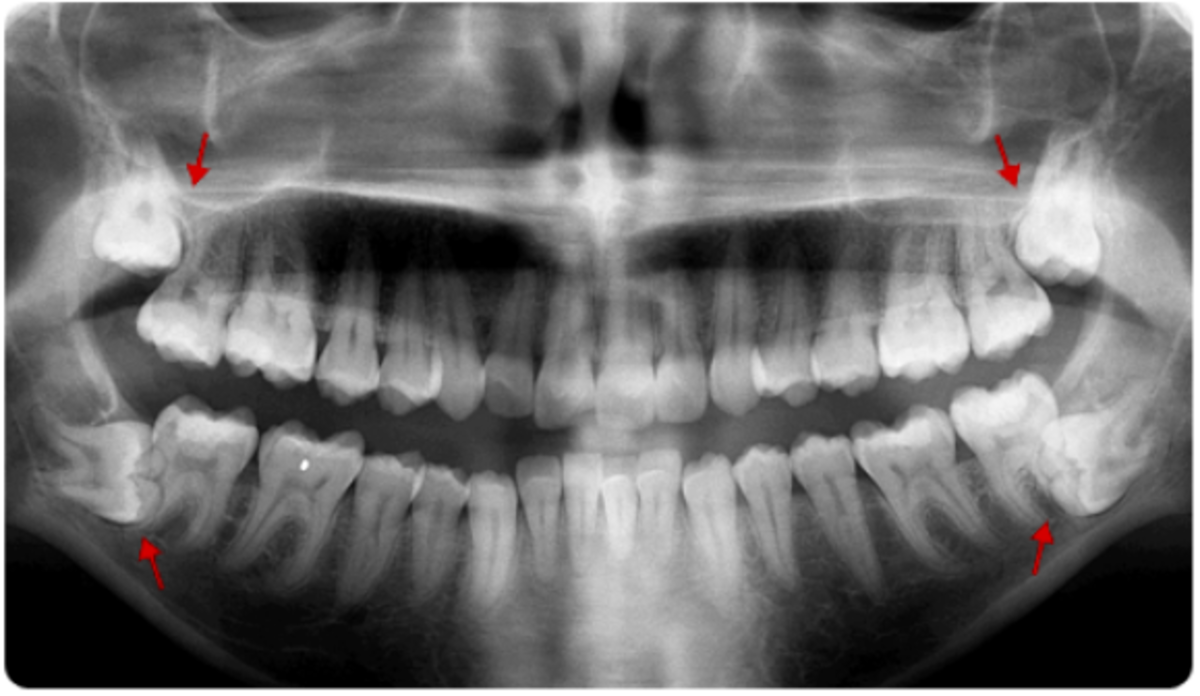

«Κατά τη διάρκεια της αρχικής εξέτασης αξιολογούμε το οδοντιατρικό και ιατρικό ιστορικό του ασθενή και κάνουμε ακτινογραφίες. Η βασική και απαραίτητη ακτινογραφία για την σωστή αξιολόγηση είναι η πανοραμική και σε κάποιες σπάνιες περιπτώσεις μπορεί να ζητηθεί και μία πιο εξειδικευμένη αξονική απεικόνιση (Denta Scan).